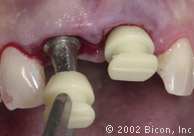

Установка двух 5.0mm x 4.0mm Stealth Shouldered Abutment

Stealth One-Piece Acrylic Sleeves

Подготовка для установки временной конструкции

Установка временной конструкции